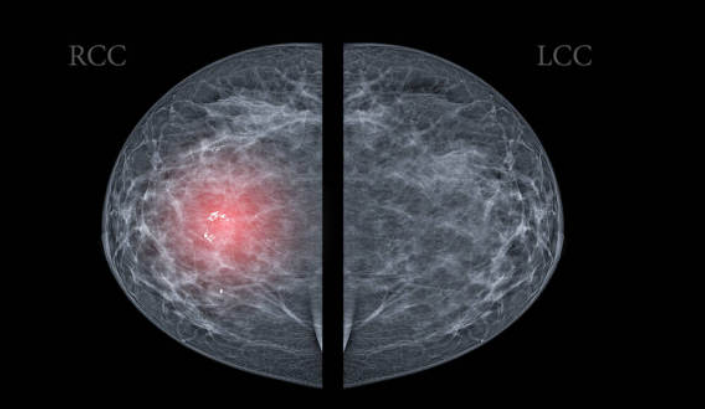

乳腺结节、甲状腺结节和肺结节是检出率最高、最常见的三类结节。

乳腺结节:不能算是一种真正的病,更多是某些疾病的表现,如乳腺增生、乳腺纤维腺瘤、乳腺癌等。乳腺结节的形成可能是乳房发生感染或损伤,或是内分泌紊乱、基因突变等刺激细胞增殖导致。

张晓军指出,推断结节的性质要通过触诊结合影像检查。乳腺结节要靠彩超、钼靶、核磁等检查;甲状腺结节要靠彩超、CT、造影检查;超过1厘米的肺结节要拍胸片,小于1厘米的要做CT及核磁检查。